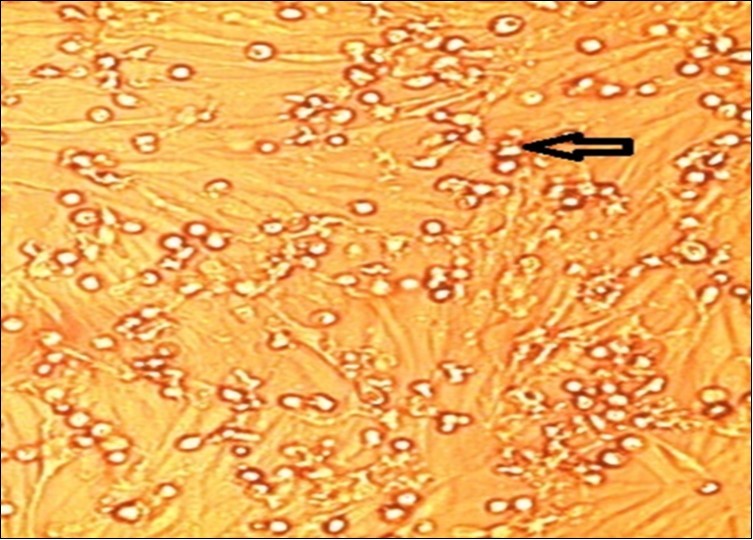

Samples used for isolation were collected from animals which showed severe clinical symptoms and FMDV positive infections with FMDV by using various serological examination. FMDV isolation trials from tissue samples were using BHK-21 cell lines. All samples were collected during active infection and from feverish animals (i.e. during circulation of viruses in blood; vireamia). Tissue culture infected cells showed cytopathic effects (CPE) in the form of rounding of cells, abnormalities on cytoplasm and cytolysis.

Figure 14.FMDV infected BHK-21 cells culture and Cyto-Pathic Effect (CPE) in the form of cells rounding and detachment, granularity of the cytoplasm and complete cell lysis.